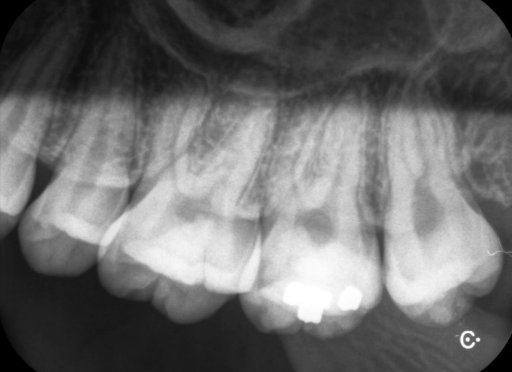

예를 들어, 일반적인 스탠다드 엑스레이는 약 3μSv로 하루치 자연 방사선의 절반 수준에 불과합니다.

치과에서의 엑스레이도 마찬가지입니다. 엑스레이 촬영이 없다면 병의 진행 상태를 정확히 파악할 수 없고,

결국에는 잘못된 치료로 이어질 가능성도 있습니다.

예를 들어, 임플란트를 하려면 턱뼈의 높이, 폭, 신경과의 거리까지 정확히 알아야 하는데,

이를 확인하지 않고 진행하면 부작용 확률이 높아집니다. 이런 상황에서는 오히려 촬영을 안 하는 것이 더 큰 위험을 초래할 수 있습니다.

실제로 저희 병원에서도 엑스레이 촬영 시 의료진은 항상 환자의 상태와 촬영 목적을 먼저 고려한 후, 필요 최소한의 촬영만을 시행합니다.